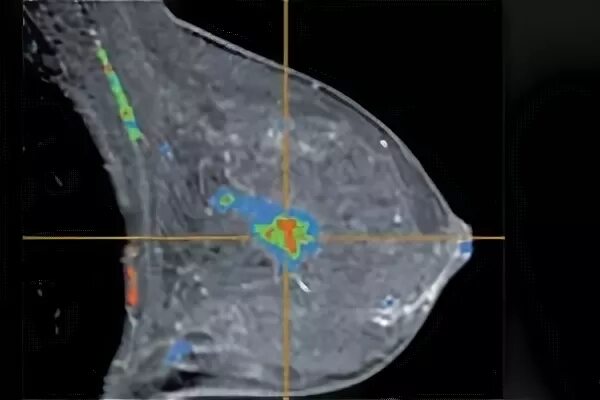

Делают ли кт молочных желез